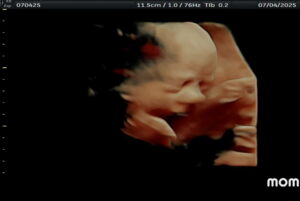

Here is the 28 week scan update of our little girl!

Patient age: 38

Tubal ligation type: Tubal rings (bands)

Patient hometown: Corry, Pennsylvania